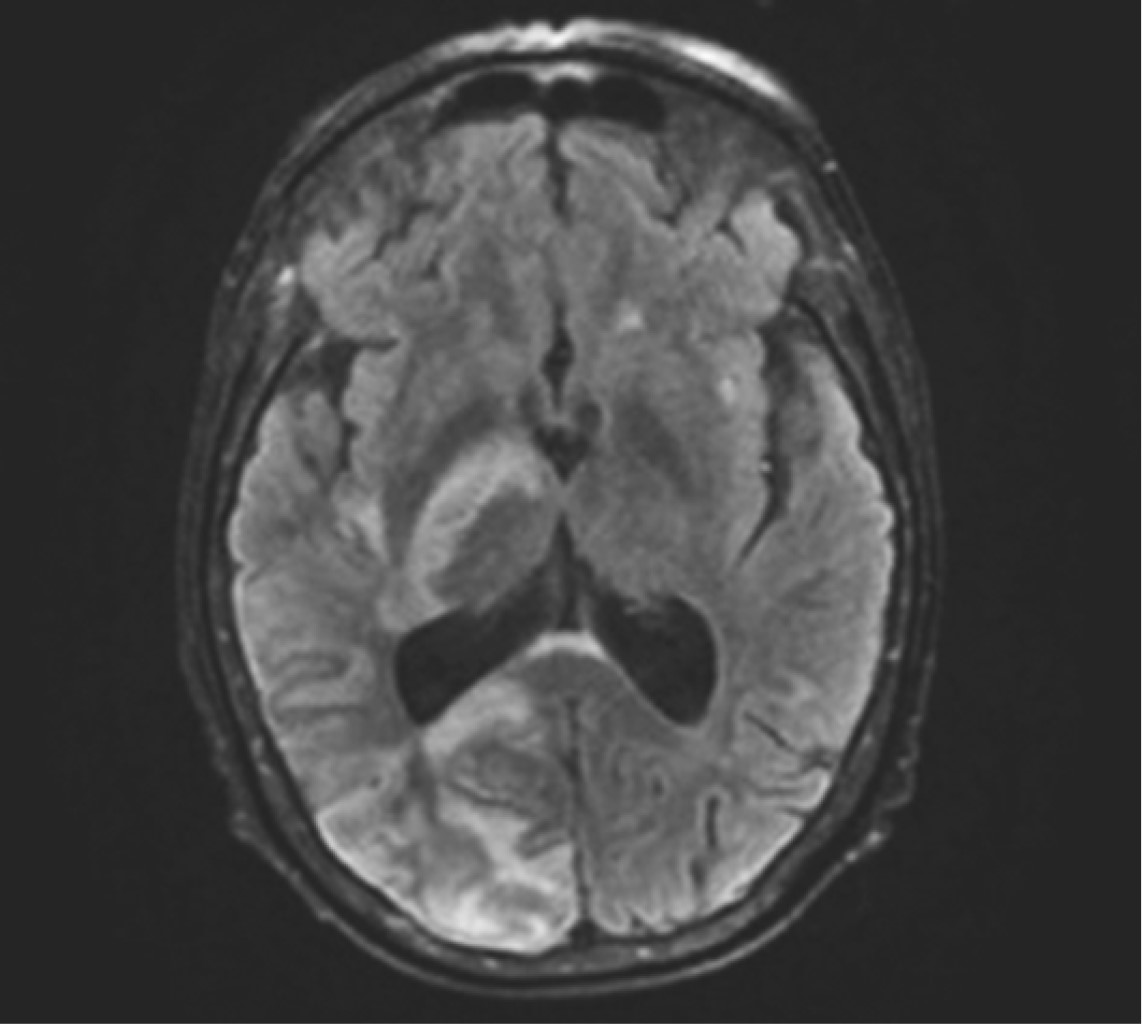

La endocarditis infecciosa en válvulas nativas o en válvulas reemplazadas quirúrgicamente ha sido ampliamente descrita en la literatura; sin embargo, respecto a la endocarditis infecciosa en válvulas bioprotésicas transcatéter, aún se encuentra en un proceso continuo de investigación. Presentamos el caso de una paciente de 66 años con diagnóstico de endocarditis infecciosa temprana de válvula protésica aórtica percutánea SAPIEN 3, quien tuvo una evolución clínica y desenlace favorable con tratamiento médico conservador basado en antibióticos, a pesar de que la incidencia de mortalidad intrahospitalaria a causa de EI-TAVR, representa más de 40%. Reportar nuevos casos clínicos con sus diferentes características, sus tratamientos y resultados obtenidos, se considera de suma importancia para apoyar a un mejor diagnóstico y tratamiento médico en futuros pacientes.

Figura 1